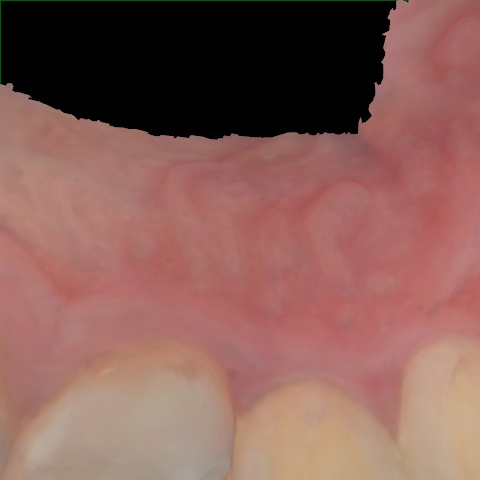

NHD39990

Annotated as "Good"

Original Image Rendering Image